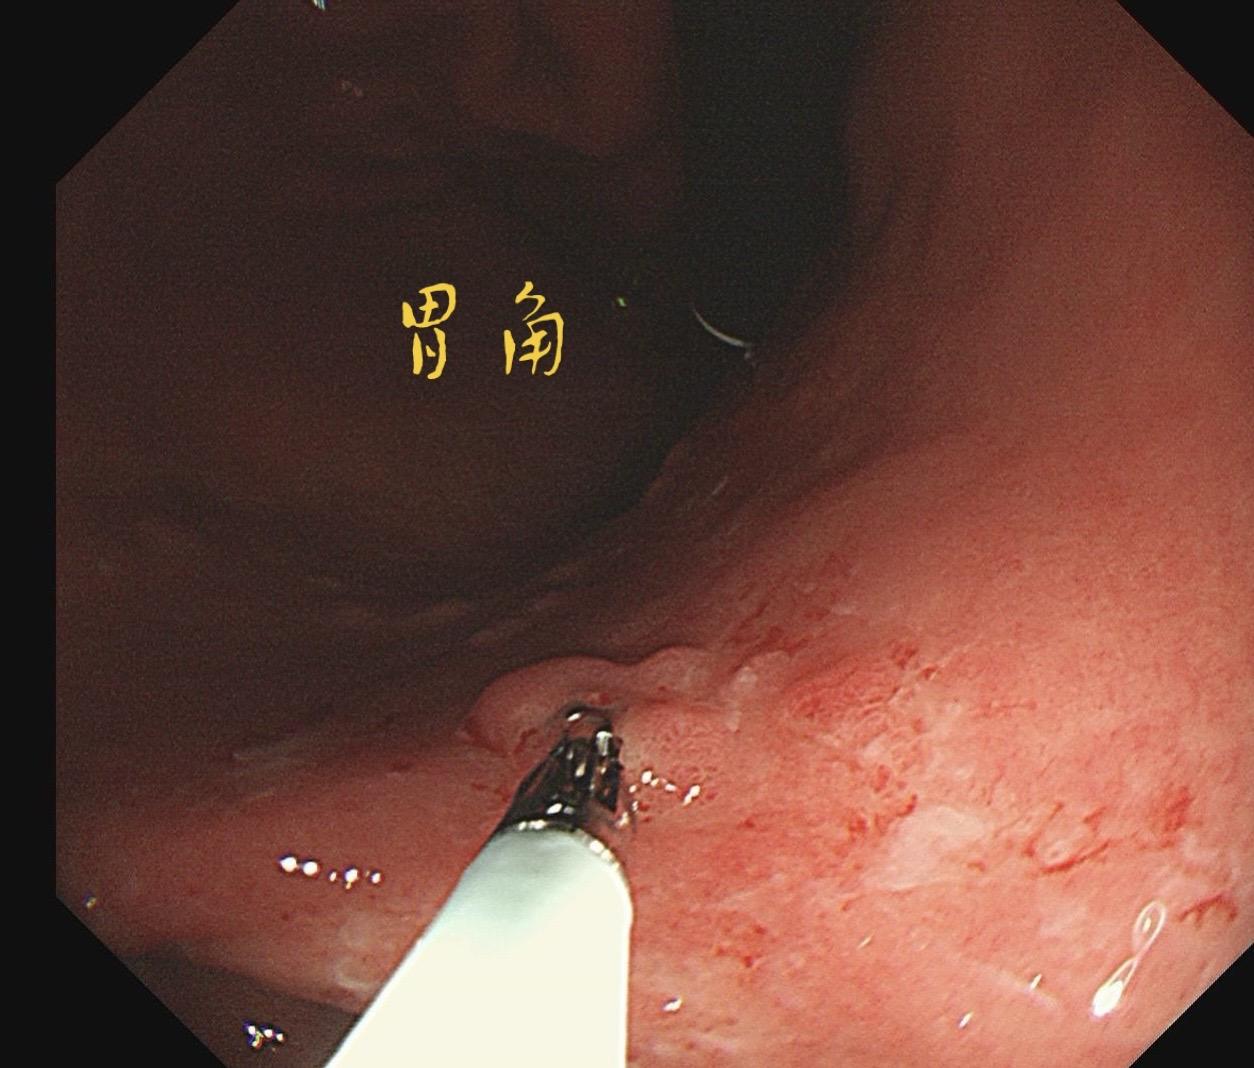

男,61岁,胃巨大褪色调病变。答案在最后一张图片,你猜对了吗? 患者因上腹部饱胀行胃镜检查,Hp阴性背景,胃窦至贲门下见一巨大褪色调病变,边界清晰,病变相对表浅,未见明显溃疡及隆起,胃壁较柔软,充气顺应性佳,予多点活检确诊,拟外科手术行全胃切除。做这么多年胃镜,还是第一次遇到这样的……